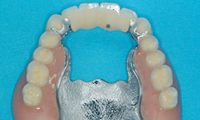

몇 개의 임플란트를 심은 뒤, 완성된 임플란트에 부분 틀니를 연결해 흔들림 없이 안정감 있게 사용할 수 있으며 스스로 탈착은 불가능합니다.

적은 수의 임플란트를 심으면서도 입안의 틀니가 움직이지 않도록 고정해 주어 식사하는 데 부담이 적습니다.